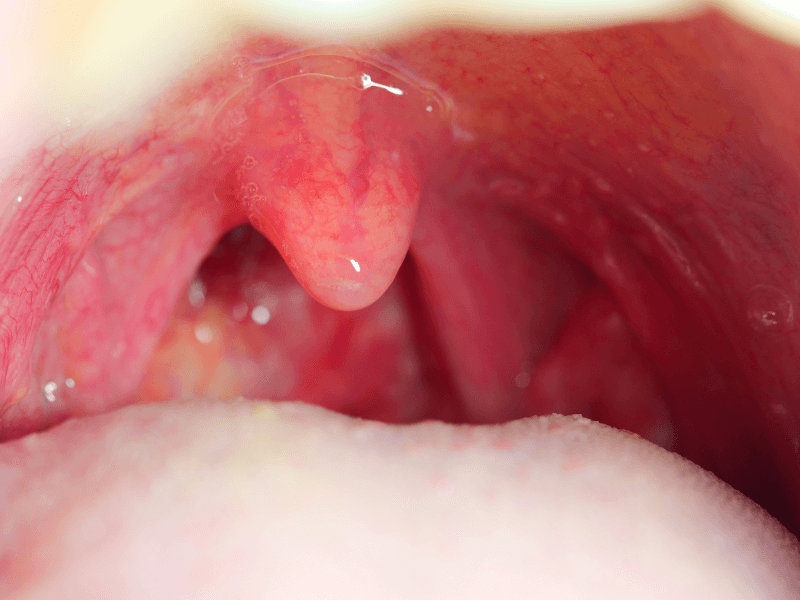

Có thể, nhưng không phải nguyên nhân thường gặp nhất. Đa số trường hợp đau họng là do virus hoặc do các yếu tố không nhiễm trùng. Viêm họng do vi khuẩn thường được nghĩ đến nhiều hơn khi đau họng rõ, amidan sưng đỏ, có mủ hoặc chấm trắng, nổi hạch cổ đau, hơi thở hôi hoặc nuốt đau nhiều.

Đau họng kéo dài không sốt nhưng kèm dấu hiệu bất thường cần được thăm khám

Bạn nên đi khám nếu có một trong các dấu hiệu sau:

đau họng kéo dài trên 1 tuần hoặc tái đi tái lại nhiều lần

nuốt đau nhiều, ăn uống khó khăn

khàn tiếng kéo dài trên 2 tuần

khó thở, thở rít, cảm giác nghẹn ở họng

nổi hạch cổ, sưng cổ

có mảng trắng, loét họng hoặc đau lệch một bên rõ

sụt cân, mệt kéo dài, hơi thở hôi bất thường

là người hút thuốc lâu năm hoặc có bệnh nền hô hấp.

Đây là những tình huống nên được khám để tìm nguyên nhân chính xác, nhất là khi triệu chứng không còn đơn thuần là kích ứng nhẹ.